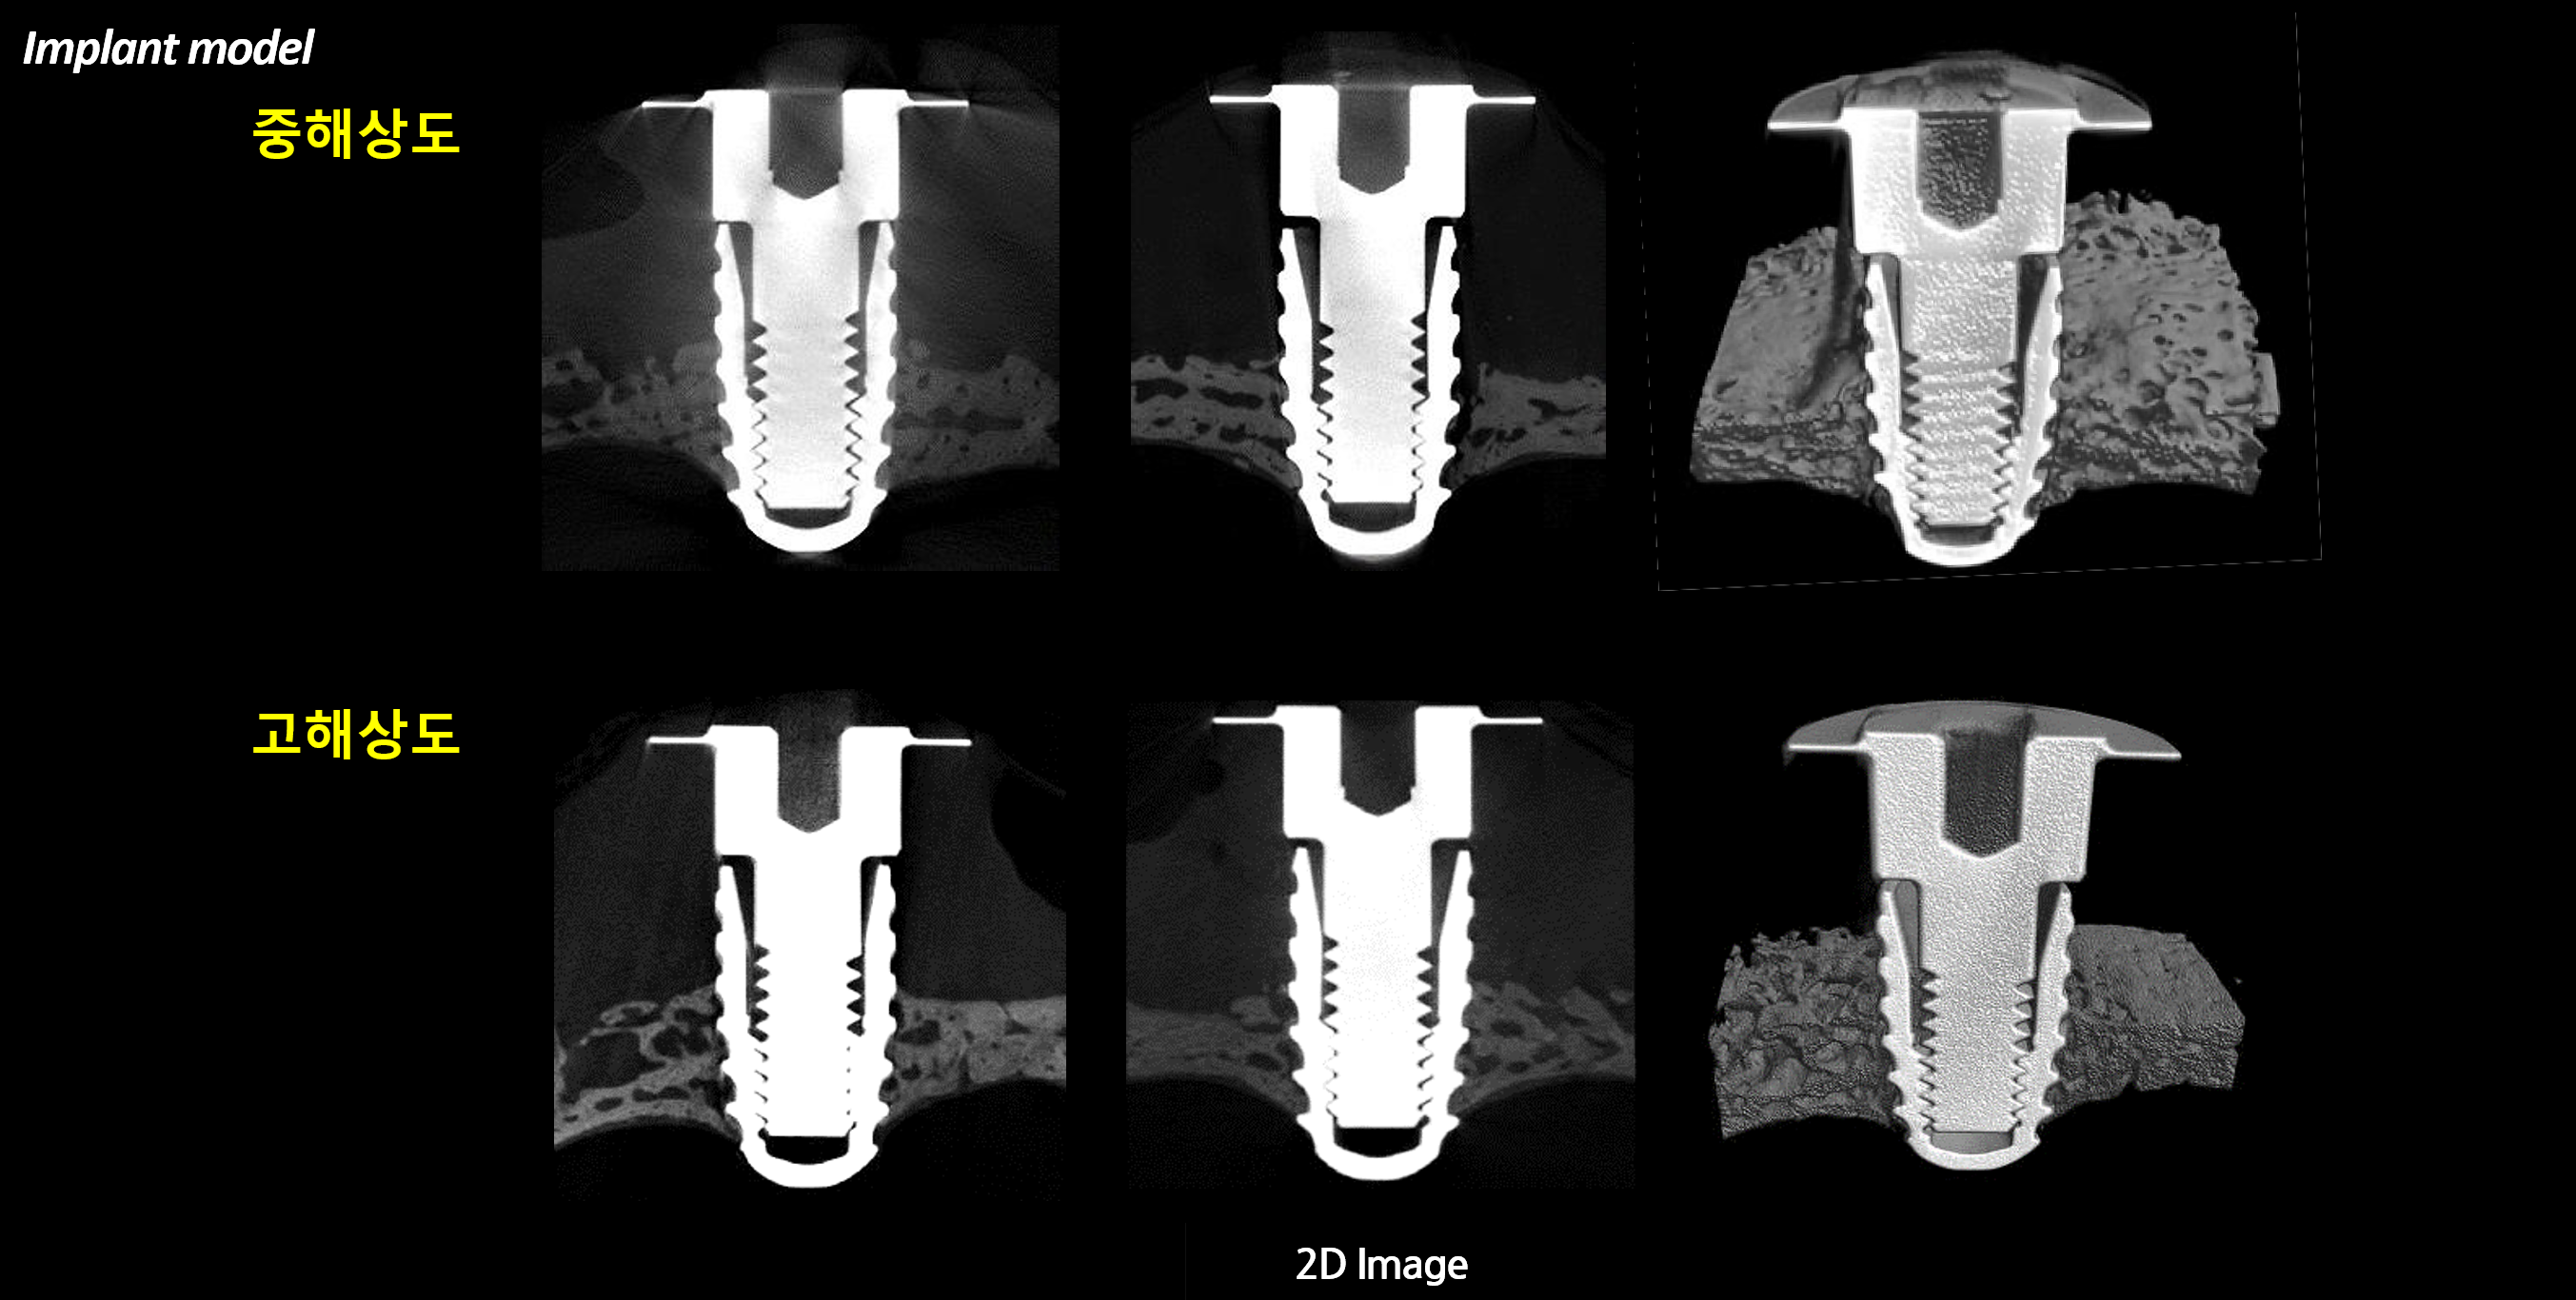

분석 예시

장비

이미지

2D & 3D 이미지 및 정량분석

Implant 체결 구조 분석

Implant